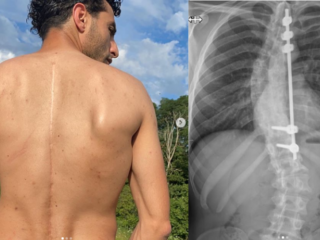

Tijdens het interview zit Touzani met een been in het gips. De straatvoetballer heeft zijn achillespees afgescheurd, maar is desondanks erg positief ingesteld. "Ik ben dankbaar dat dit is gebeurd", zegt Touzani, terwijl hij zich ervan bewust is dat het voor veel mensen raar klinkt dat hij blij lijkt te zijn met zijn blessure.

De blessure kwam voor Touzani op een vervelend moment. Het gebeurde op de dag dat zijn biologische vader bij hem in zou trekken. "Mijn vader werd op jonge leeftijd al heel erg ziek. Hij kreeg een psychose, had last van schizofrenie en een dwangneurose. Ik ben zolang bezig geweest om mijn vader bij mij in te laten trekken. Ik heb lange tijd niet veel kunnen doen, maar het is een prachtige droom die nu is uitgekomen."